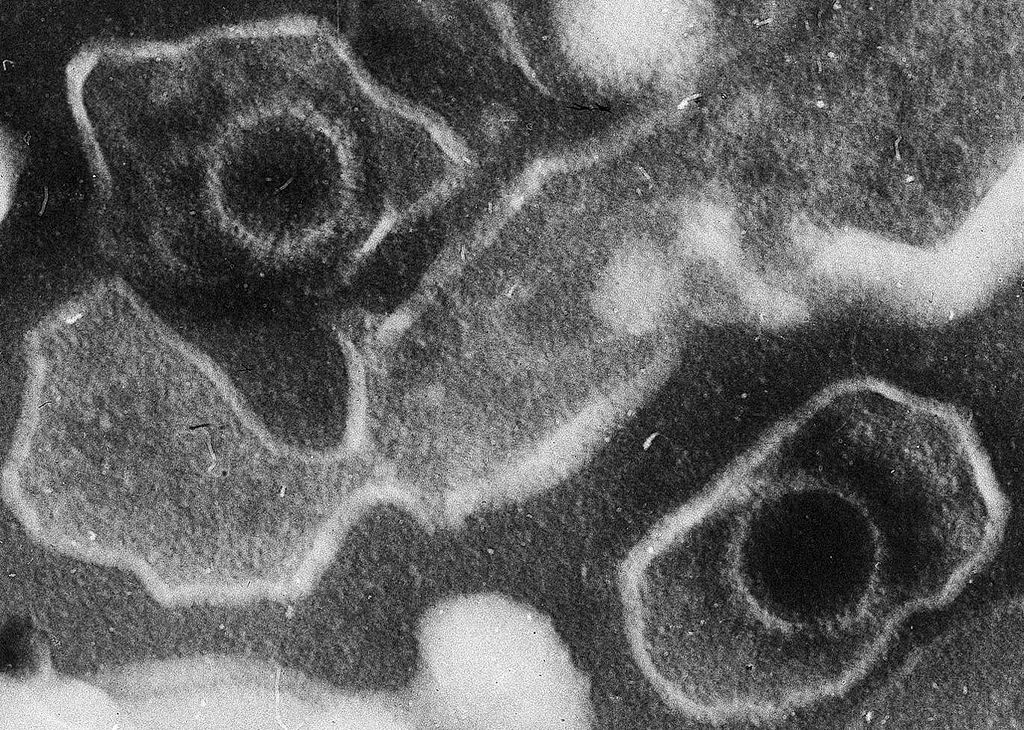

电子显微镜的水痘带状疱疹病毒约放大倍数为150,000倍

人类疱疹病毒

EBV病毒